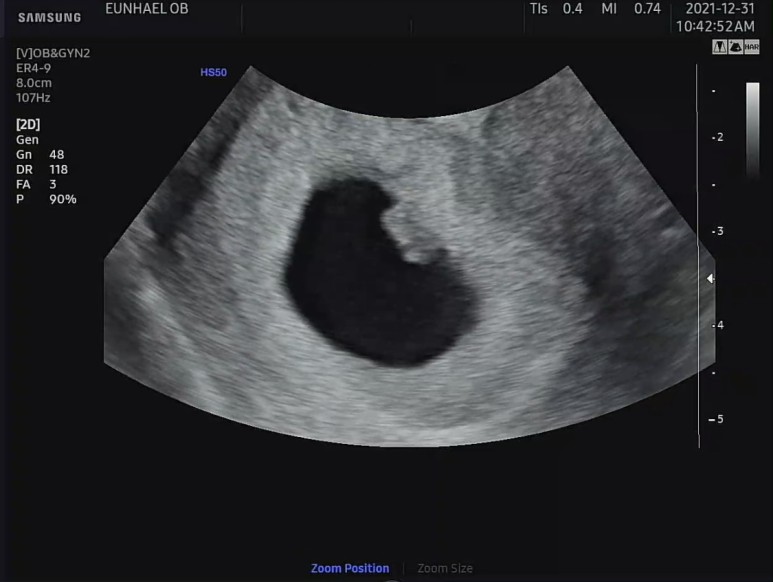

아침 일찍 병원에 가서 질 초음파를 하고, 우선 아기가 잘 있는지 확인했다

아가는 심장도 잘 뛰고 다행이 아주 건강했다. 이틀 전에 병원에서 도마뱀 모양의 초음파를 봤었는데, 이틀 전 모양과는 또 다른 모양의 아기가 초음파 속에 있었다. 아기집도 그새 좀 더 커져 있었다.

초음파 상에서 자궁벽 주변으로 피고임이 보였다.